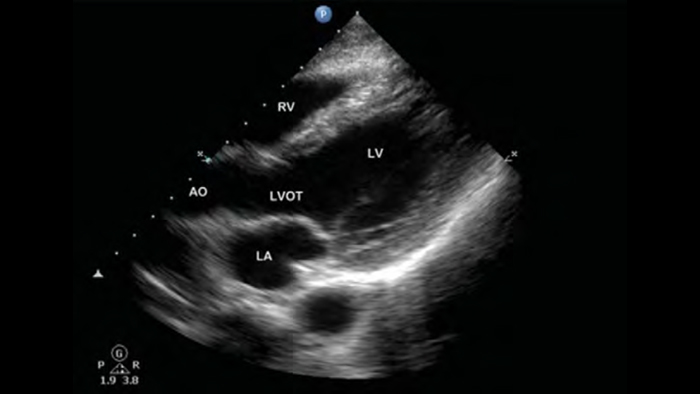

• 4 to 1 MHz extended operating frequency range • 2D, color Doppler, M-mode, advanced XRES and multivariate harmonic imaging • High-resolution imaging for abdominal and cardiac applications: Cardiac, OB/GYN, Lung, Abdomen and FAST imaging preset optimizations

From revealing the subtle details of an image to uncovering enriched tissue definition from multiple angles, Lumify can help you make real-time decisions with more confidence from assessment through recovery.